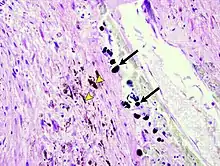

Micrograph of the spleen showing darkly stained, spheroid Gamna-Gandy bodies (arrows) outside the vessel wall at the center. Also shown is diffusely scattered, brown, granular hemosiderin pigment (arrowheads), indicating previous hemorrhage (hematoxylin & eosin staining, 40x magnification).